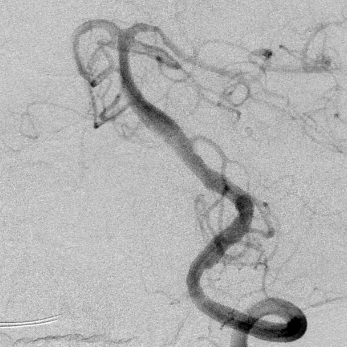

椎基底动脉冗长扩张症,是最棘手最复杂的脑血管病之一。患者从外地千里迢迢(3900余公里,仅高铁41小时)赶来东方医院诊治,期间症状不断加重(图2非真实大小)。术后一周复查:1、右侧肢体肌力明显改善;2、右侧肢体和枕部麻木症状明显改善;3、饮水呛咳缓解;4、共济失调明显改善;5、流涎消失;6、消失的味觉再次恢复。术后一周复查:血管修复良好(图5)。期待患者早日康复,早日奔赴工作岗位,保一方平安。